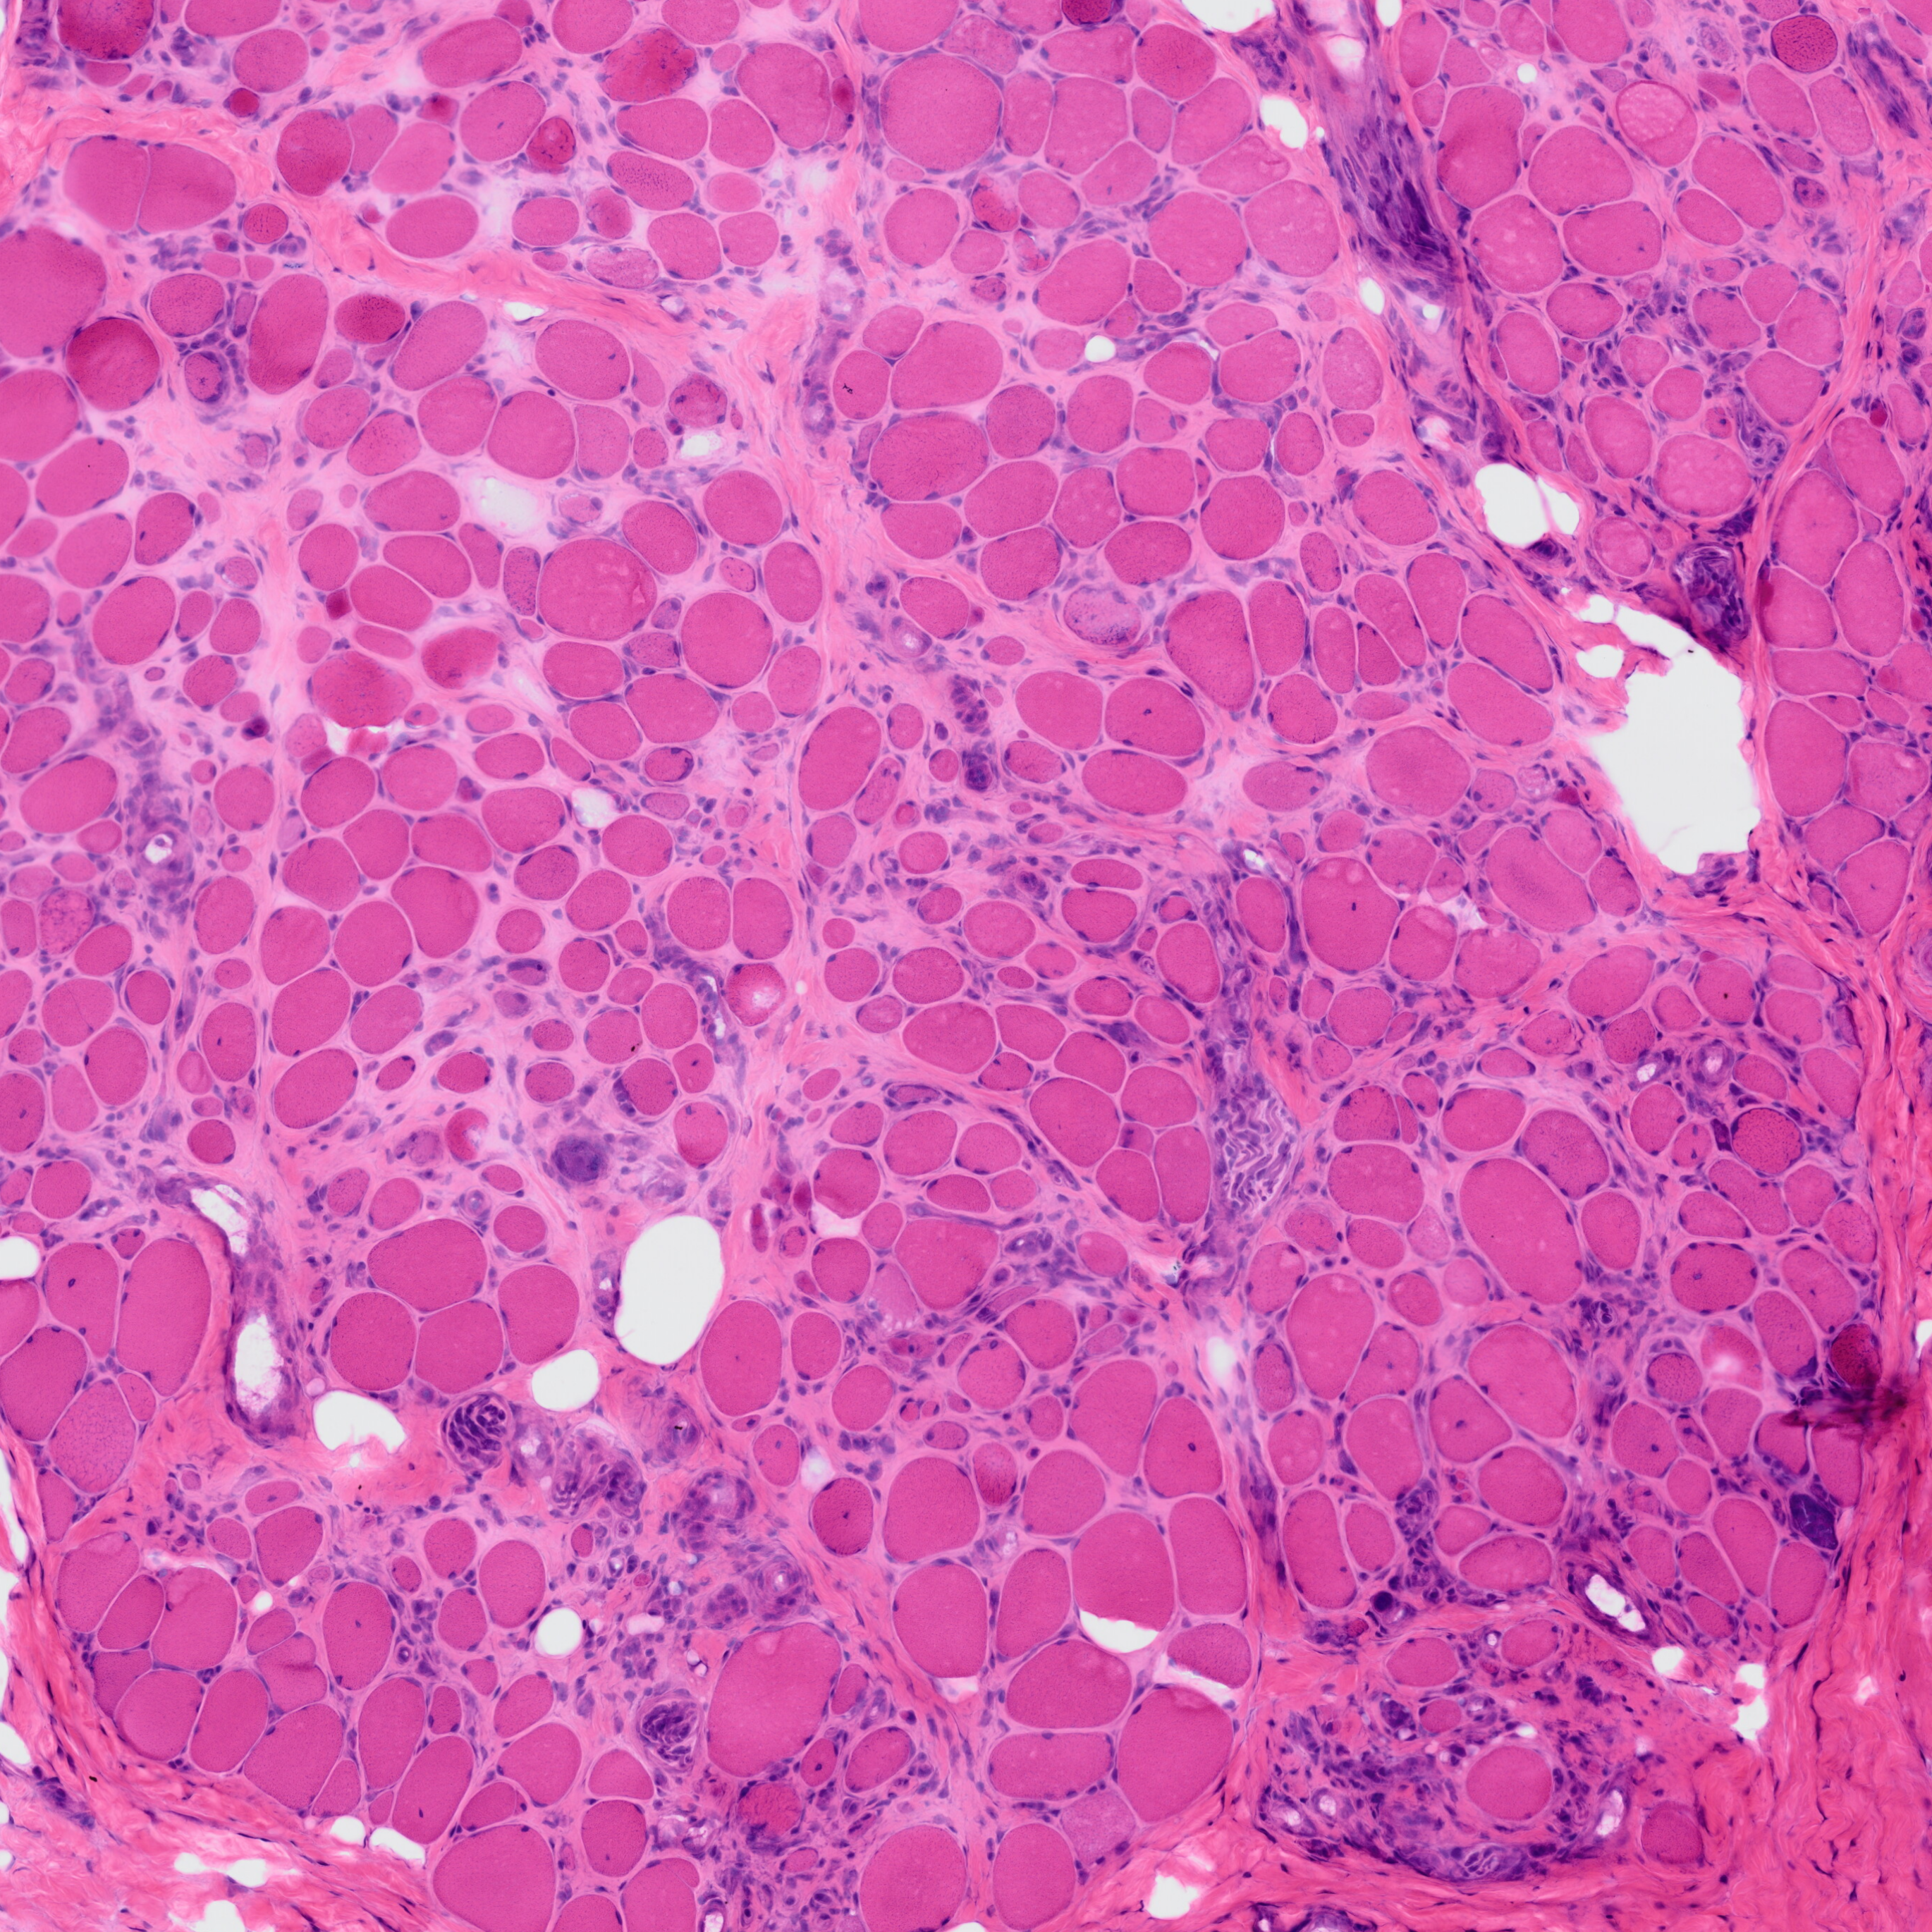

MyoPath is a deep learning pipeline for objective morphometric assessment of skeletal muscle biopsies from routine H&E-stained whole slide images (WSI).

MyoPath implements a four-tissue segmentation pipeline — Cellpose-SAM for myofiber instance segmentation, a pixel classifier for fat infiltration, watershed detection for nuclei, and Boolean subtraction for connective tissue — to extract 37 morphometric features per sample. From these, seven clinically interpretable pathology indicators are derived, with Nuclear Centralization Index (NCI) and Fiber Size Variability Coefficient (Fiber CV) serving as primary biomarkers.

- Four-tissue segmentation: Myofiber, fat, nucleus, and connective tissue from a single H&E section